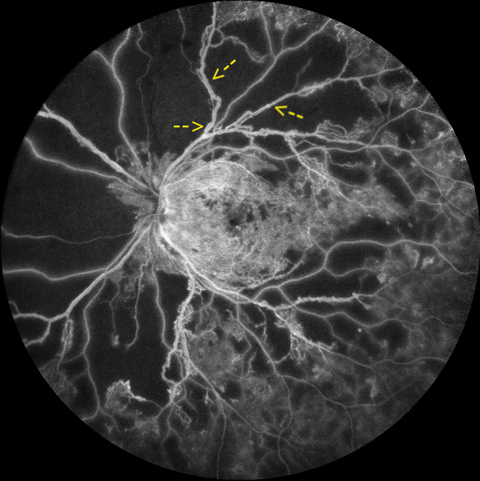

Proliferative diabetic retinopathy